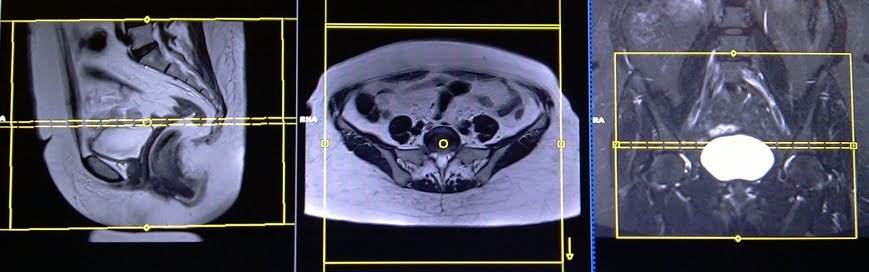

T2 tse axial 5 mm big fov

Plan the large FOV axial slices on the coronal plane; angle the positioning block parallel to the line along the right and left hip joint. Verify the positioning block in the other two planes. Establish an appropriate angle horizontally across the pelvis in the sagittal plane. The slices should be sufficient to cover the entire pelvis from the iliac crest down to two slices below the symphysis pubis. The FOV should be large enough to cover the whole pelvis (normally 350mm-400mm). Additionally, adding saturation bands on top of the axial block will reduce artefacts from arterial pulsation and breathing.

Parameters

TR 4000-5000 | TE 100-120 | SLICE 5 MM | FLIP 130-150 | PHASE A>P | MATRIX 384X384 | FOV 350-400 | GAP 10% | NEX(AVRAGE) 2 |